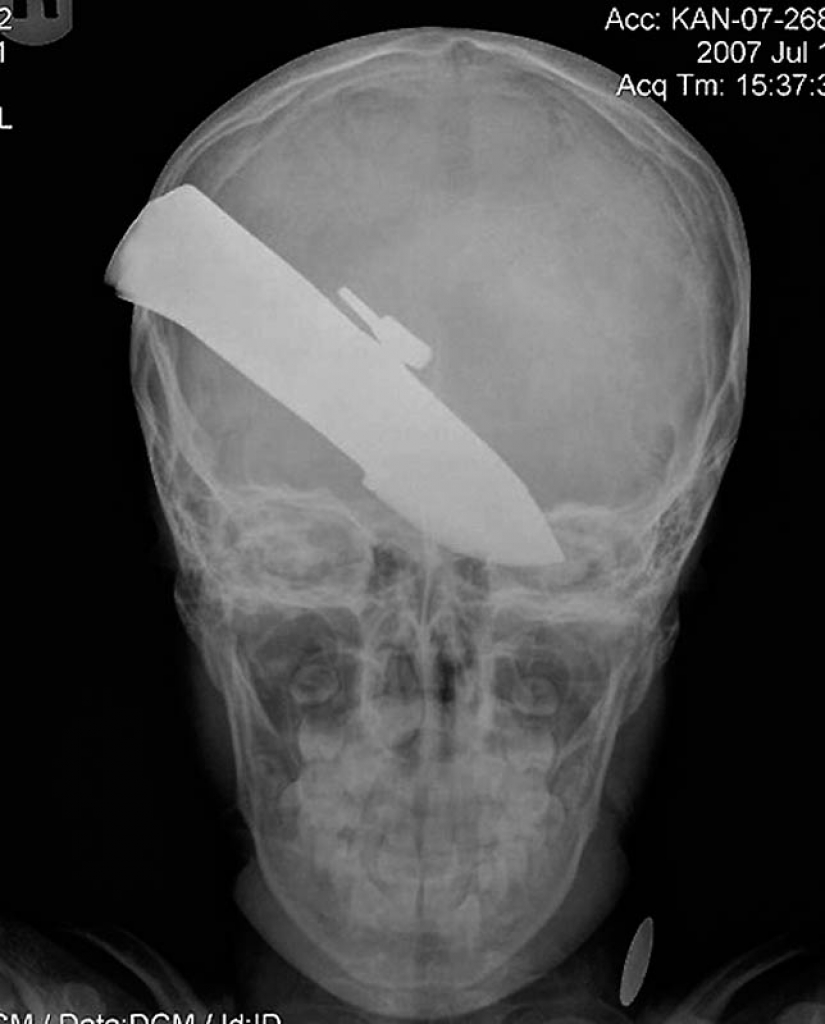

15. Knife in the head 10 year old boy. The boy survived.